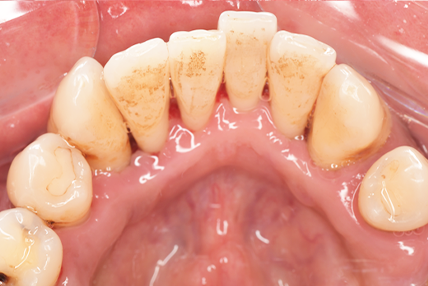

CASE 7

Before

After

基本情報

| 年齢・性別 | 48歳・男性 |

|---|---|

| 主訴 | 定期検診 |

| 治療内容 | スケーリング |

| 治療期間 | 60分 |

| 治療費 | 1,500円(保険診療) |

| リスク・副作用 | 知覚過敏、出血 |

| 治療方針 | まず歯肉縁上歯石を除去して、スッキリとした感覚や滑らかな舌ざわりを実感してもらいました。この状態を保てるように歯磨きの仕方や、歯周病についてお話ししました。 今後は歯肉縁下歯石を除去して、歯周病治療を行っていきます。 |

| 担当者所見 | 久しぶりの歯科医院への受診でした。 治療に慣れていないため、少しずつ歯石を除去していきました。 |